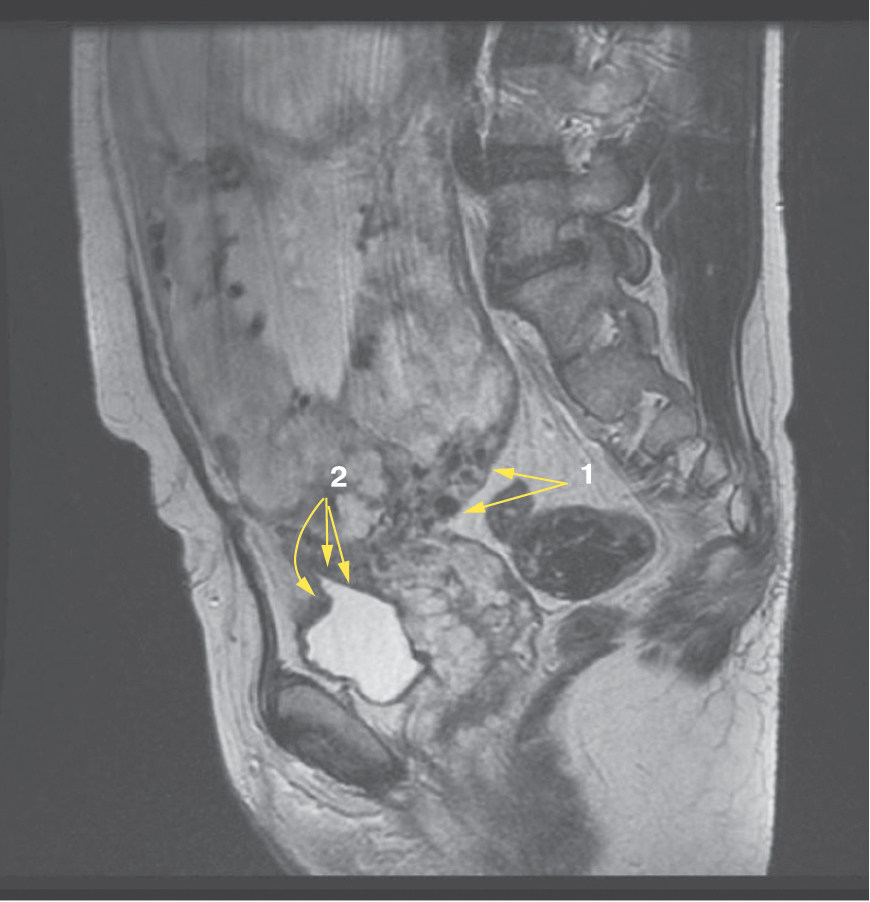

Является ли симптом «обнаженного сосуда» патогномоничным для параметральной инвазии или нет, еще предстоит выяснить; однако в ходе исследования установлена его связь с частотой гистерэктомий в группах с наличием симптома «обнаженного сосуда», что, вероятно, обусловлено мощной сосудистой сетью коллатералей и неоангиогенезом. Во всех случаях обнаружения данного признака впоследствии была выполнена вынужденная гистерэктомия (рис. 3–6, пациентка Н., 37 лет).

Рис. 5. Корональная проекция МРТ. 1 – интрамуральная гиперваскуляризация; 2- измененный контур мочевого пузыря